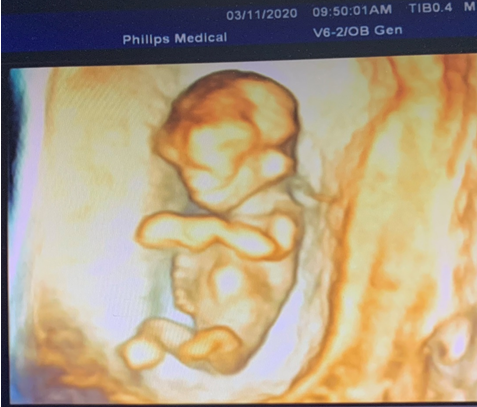

孕11-13周+6天要做一项重要的检查——颈项透明层厚度(NT)检查。随着“二孩”政策开放,高龄孕妇数量明显增多,早期NT检查显得特别重要。NT的异常增厚与胎儿畸形尤其是染色体异常有着密切的关系。NT检查适宜的孕周是11-13+6周,也就是头臀长在45-84mm之间。

这次检查除了NT的测量外,还需要观察一些软指标,如胎儿鼻骨是否存在、静脉导管血流频谱等,来综合判断胎儿有无染色体异常的风险。同时结合母体血清学检查,染色体异常宝宝的检出率可达90%以上。另外,这个阶段也能对胎儿的大体结构作一个初步的检查,对于一些严重的畸形早诊断、早处理,大大减轻孕妇身体及心理伤害。早孕期超声可以筛查出的胎儿畸形包括:无脑儿/露脑畸形,胎儿水囊瘤,腹壁畸形如脐膨出、腹裂/严重的内脏外翻,严重的肢体残缺等比较明显的畸形。而对于双胞胎宝宝的妈妈来说,这个时期的检查还有一个很重要的事情,就是确定双胎妊娠的绒毛膜性质,这对于将来中、晚孕期的检查以及临床医生的处理方法至关重要。

我科拥有先进的四维彩超设备,让准妈妈们在早孕期也能够观察到宝宝可爱、萌萌的样子。